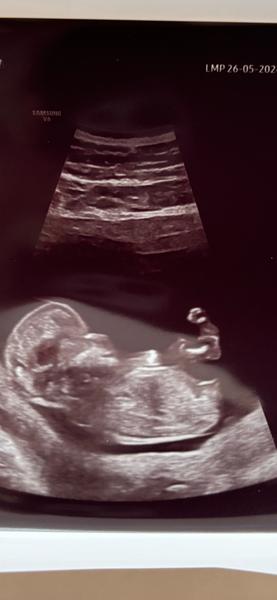

podle fotografií to vypadá spíše na pohlaví ženské, ale určitě nic nekupujte, nemalujte, apod. a vyčkejte na ultrazvuk ve 20. týdnu, protože v I. trimestru to lze jen odhadovat a často, i když to vypadá v I. trimestru jednoznačně, je ve 20. týdnu vše jinak 🙂